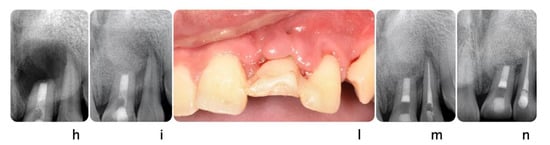

Figure 5.

Clinical scenario of a 17 years-old adolescent hit by a baseball ball in the anterior maxillary region. The boy presented to the Periodontal Department at Tufts University, Boston USA with crown fracture of left central incisor (#9) (a,b). Peri-apical radiograph show apical radiolucency, sign of necrosis. After the diagnosis, CaOH2 was applied. The root canal definitive treatment was completed but after 2 months the patient still presented with a fistula, that was tracked via a gutta-percha point. A CBCT scan was performed in order to diagnose the extent of the peri-apical lesion (c in sequence). The extent of the lesion did not suggest an endodontic therapy revision. Exploratory surgery was performed in order to rule out tooth fracture (d). The apex was resected in order to access the palatal aspect of the tooth. A PA radiograph was taken in order to verify correct apex resection and endodontic retrograde seal (e). Due to active patient skeletal growth, a decision was made to enucleate the endodontic cyst and treat the cavity with bone grafting material, in order to preserve the site for future implant placement (f,g). PA radiograph comparison before and after grafting placement (h,i). The patient was followed up for 2 months, and a fistula was identified apical to #9 (l). Tooth #10 was diagnosed as necrotic. A root canal was performed (m) and the apical radiolucency and fistula were resolved at 1 month follow up (n).